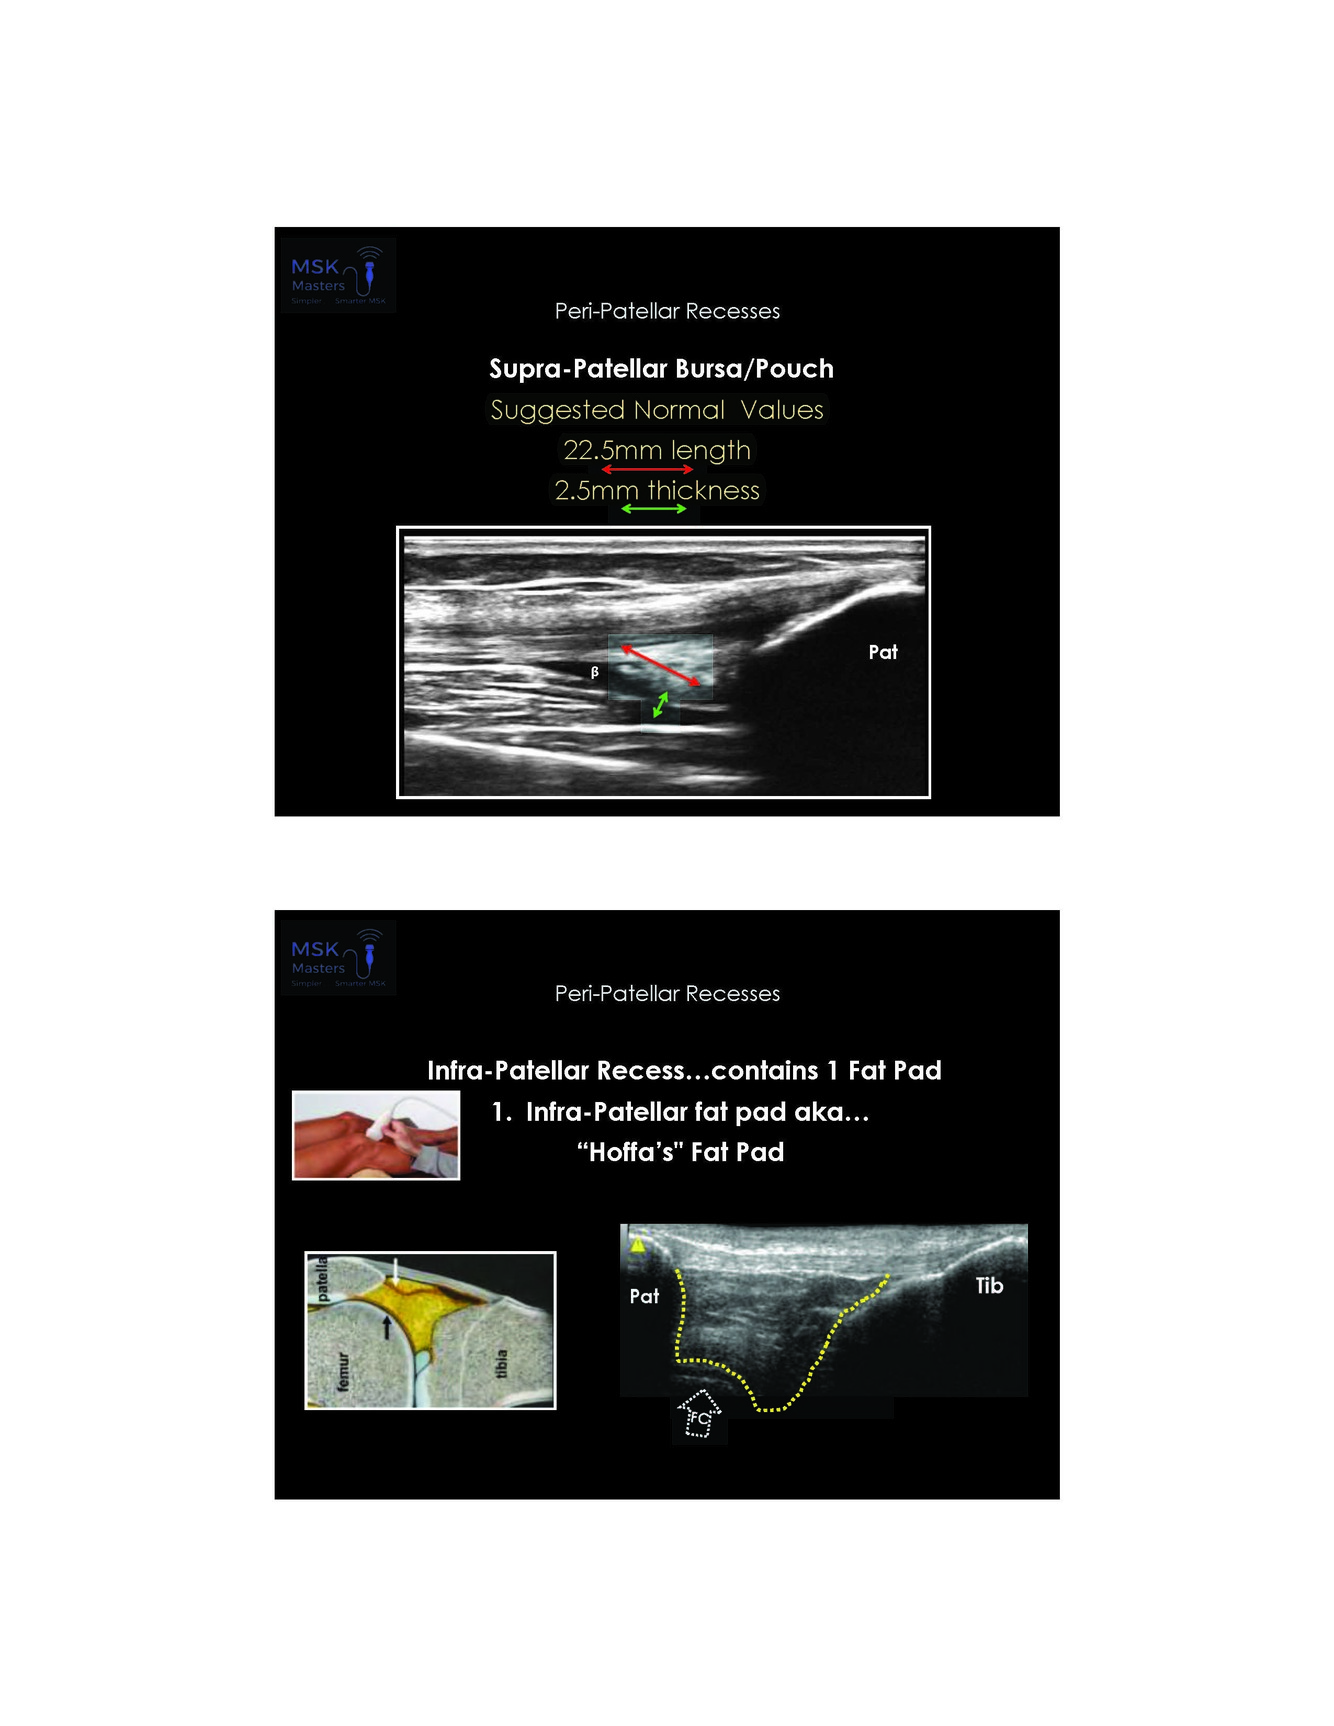

What is the suggested normal for supra patellar bursa length and thickness

22.5 mm length and 2.5 mm thickness